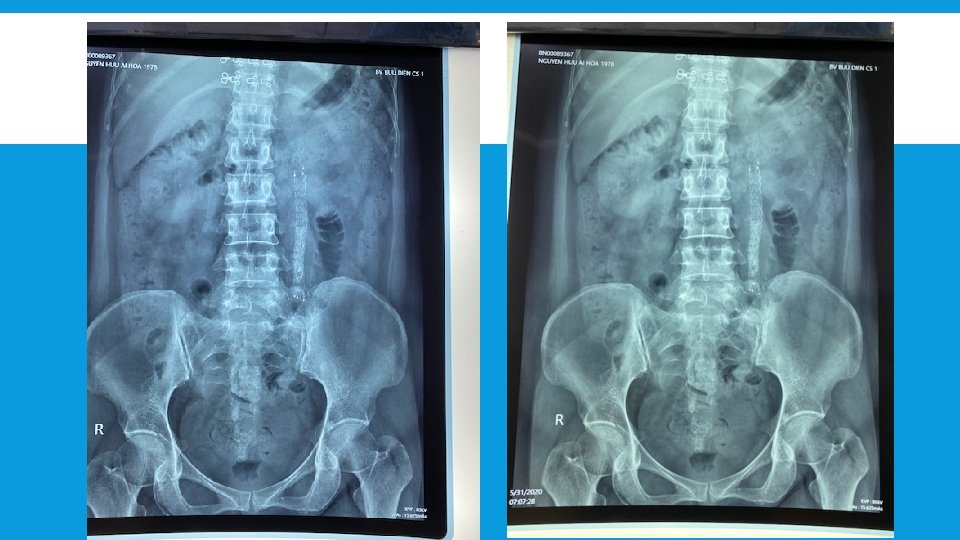

SỎI BÁM STENT Bn: Nguyễn Hữu Ái Hoa 1978 Bn đặt stent kim loại # 19 tháng, không kiểm tra thường xuyên

SỎI RỚT KẸT VÀO ĐẦU TRÊN STENT Bn: Lê Khắc Diễm Hân 1976 Khi stent # 20 tháng thì siêu âm: thận phải ứ nước độ 2 -3